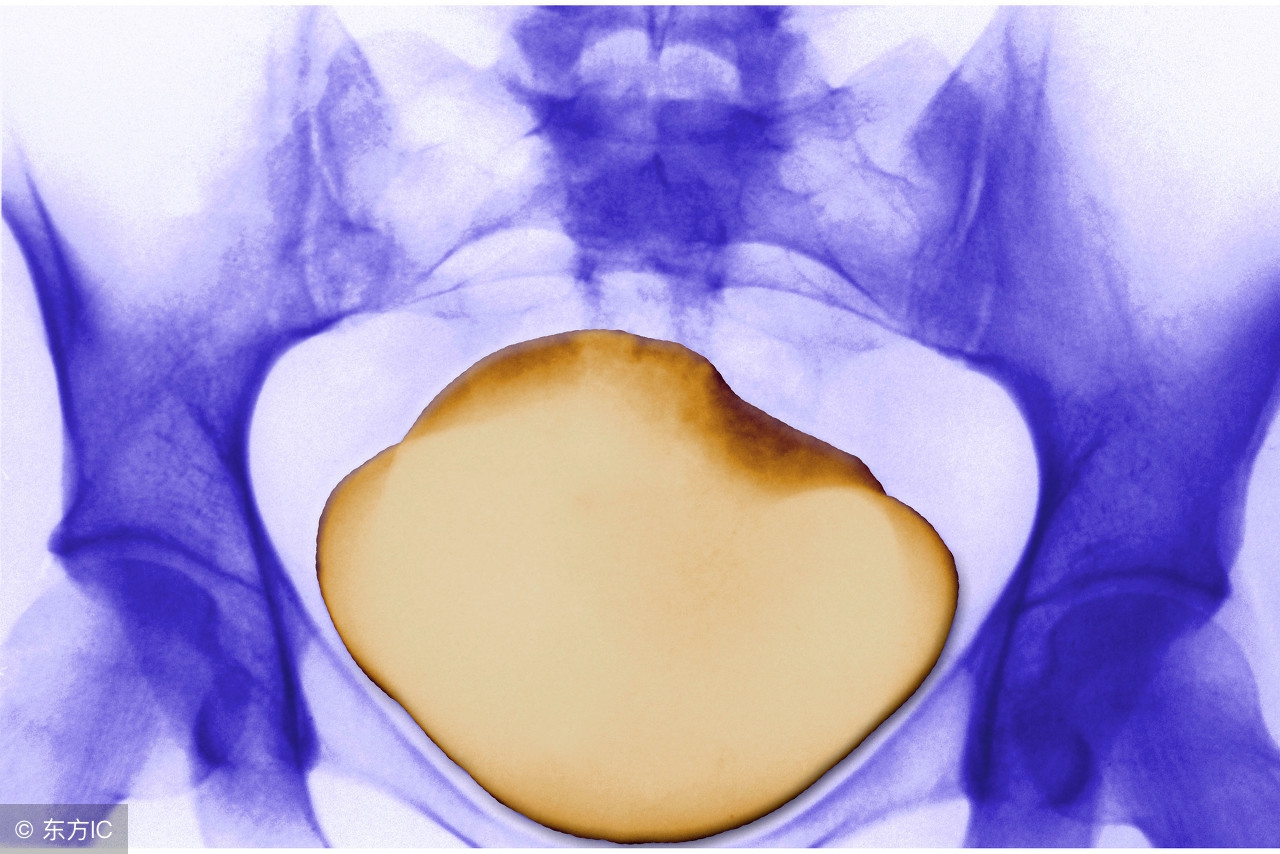

1、排尿突然中断伴尿道口刺痛或尿潴留:见于膀胱、尿道结石或尿路异物。

2、排尿不畅伴尿道口刺痛:老年男性多提示前列腺增生,亦可见于尿道结石。

3、排尿终末时尿道口刺痛,且合并尿急者,病变多在膀胱,常见于急性膀胱炎。

4、排尿开始时尿道口刺痛,或合并排尿困难者,病变多在尿道,常见于急性尿道炎。

5、排尿时尿道口刺痛或烧灼痛:多见于急性炎症刺激,如急性尿道炎、膀胱炎、前列腺炎、肾盂肾炎。

6、排尿末尿道口刺痛,排尿后仍感疼痛,或觉“空痛”,或不排尿亦痛者,病变多在尿道或邻近器官,如膀胱三角区炎、前列腺炎等。